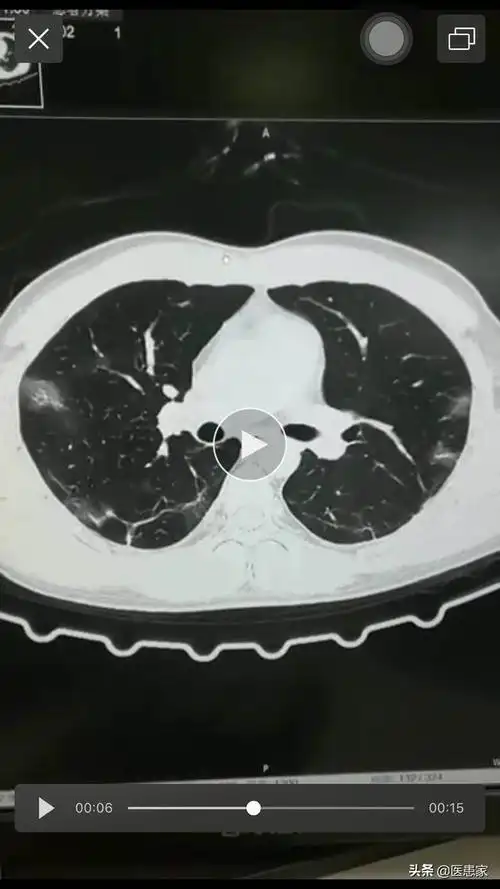

和大家认识一下这就是新冠大白肺的样子病毒性肺炎

新冠肺炎出现"大白肺",黏液阻挡氧气,看医生洗洗肺

直观展示!3d呈现新冠患者肺部影像,两肺絮状,阴影临摹均呈现